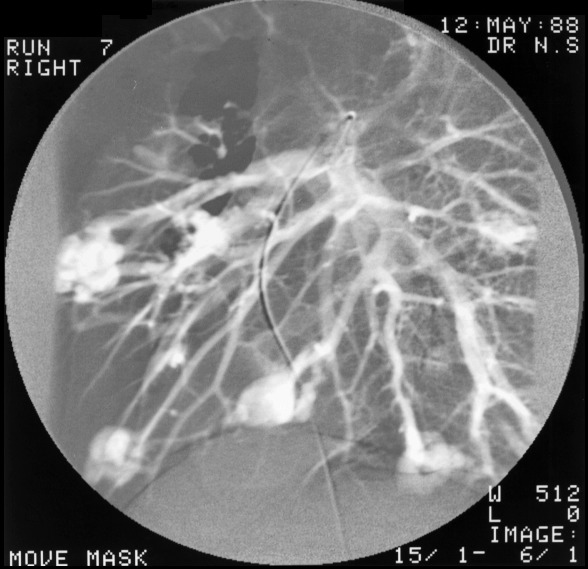

This 18 year boy had an abnormally high haemoglobin and tired easily. There were small blue venous spiders around his lips. Note the variety of rounded densities in both lungs.

Embolisation was begun and we can see several coils in situ on the right.

But eventually the number of aneurysms which needed to be closed was very large and most of the pulmonary circulation would be occluded. For this reason, the right middle lobe was surgically removed.

Several lesions were embolised on the left side

The patient was reexamined several years later and many more small fistulae had opened up in the interval.